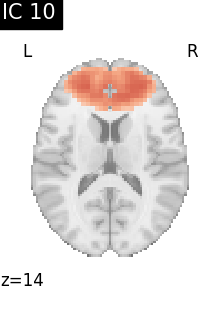

Finally, we plot the map for each ICA component separately

for i, cur_img in enumerate(iter_img(canica_components_img)):

plot_stat_map(

cur_img,

display_mode="z",

title=f"IC {int(i)}",

cut_coords=1,

vmax=0.05,

vmin=-0.05,

colorbar=False,

)

show()